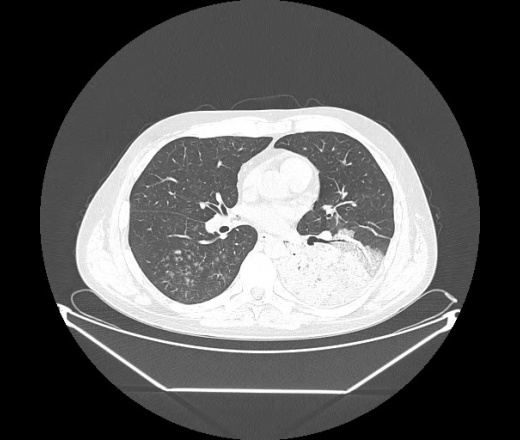

М. 1984 г.р.  Лихорадка 39, кашель , одышка.. и надоевший всем вопрос- "типично ли для ковид?" ( в настоящее время на него обязательно нужно дать ответ в своем протоколе)

На мой взгляд нетипично для ковид: много центрально-расположенных поражений, лобарное поражение нижней доли слева. 50/50

Не типичая картина для ковид.

КТ-признаки двусторонней бактериальной пневмонии.

Все верно, здесь абсолютно нетипичная картина, несмотря на матовое стекло с ретикулярными изменениями, но почему-то  посчитали иначе. Кстати,  "малыша" не заметили)?

Добавил 6 день

Что за малыш? Будущий абсцесс? Не заметил. Только о туберкулёзе подумал

+ 1?  Зона очень похожа была на формирующийся абсцесс, даже по рентгенпризнакам. Еще хотела спросить, но постеснялась. А на контроле видно

да, это я о абсцессе.